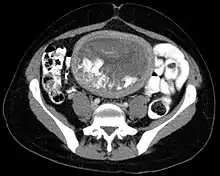

The diagnosis is strongly suggested by ultrasound (sonogram), but definitive diagnosis requires histopathological examination. On ultrasound, the mole resembles a bunch of grapes ("cluster of grapes" or "honeycombed uterus" or "snow-storm").[14] There is increased trophoblast proliferation and enlarging of the chorionic villi, and angiogenesis in the trophoblasts is impaired.[15]

A hydatidiform mole is a pregnancy/conceptus in which the placenta contains grapelike vesicles (small sacs) that are usually visible to the naked eye. The vesicles arise by distention of the chorionic villi by fluid. When inspected under the microscope, hyperplasia of the trophoblastic tissue is noted. If left untreated, a hydatidiform mole will almost always end as a spontaneous abortion (miscarriage).

Based on morphology, hydatidiform moles can be divided into two types: in complete moles, all the chorionic villi are vesicular, and no sign of embryonic or fetal development is present. In partial moles some villi are vesicular, whereas others appear more normal, and embryonic/fetal development may be seen but the fetus is always malformed and is never viable.